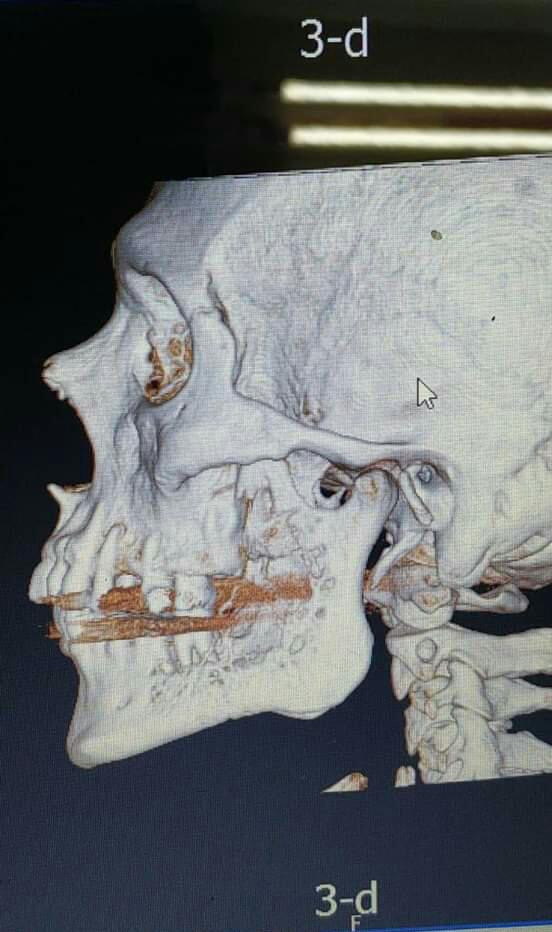

Squamous cell Carcinoma سرطان في الفك

لم يتوقع مهند أن يكون الإجراء الذي تلا التشخيص النهائي مؤلماً وصعباً إلى ذلك الحد؛ عملية جراحية يتم فيها إزالة نصف الفك السفلي من جهة اليسار.. العظام، قاعدة اللسان حتى الشفة الضاحكة، أي أنه سيدخل لإجراء عملية ستستمر لعشر ساعات لن يخرج منها كما كان أبداً، بل وستبدأ من بعدها سلسلة طويلة من جلسات العلاج الكيماوي والنووي.. انتهت العملية تاركةً خلفها قطع البلاتين المزروعة في فكه، وخرطوماً في معدته من أجل التغذية..